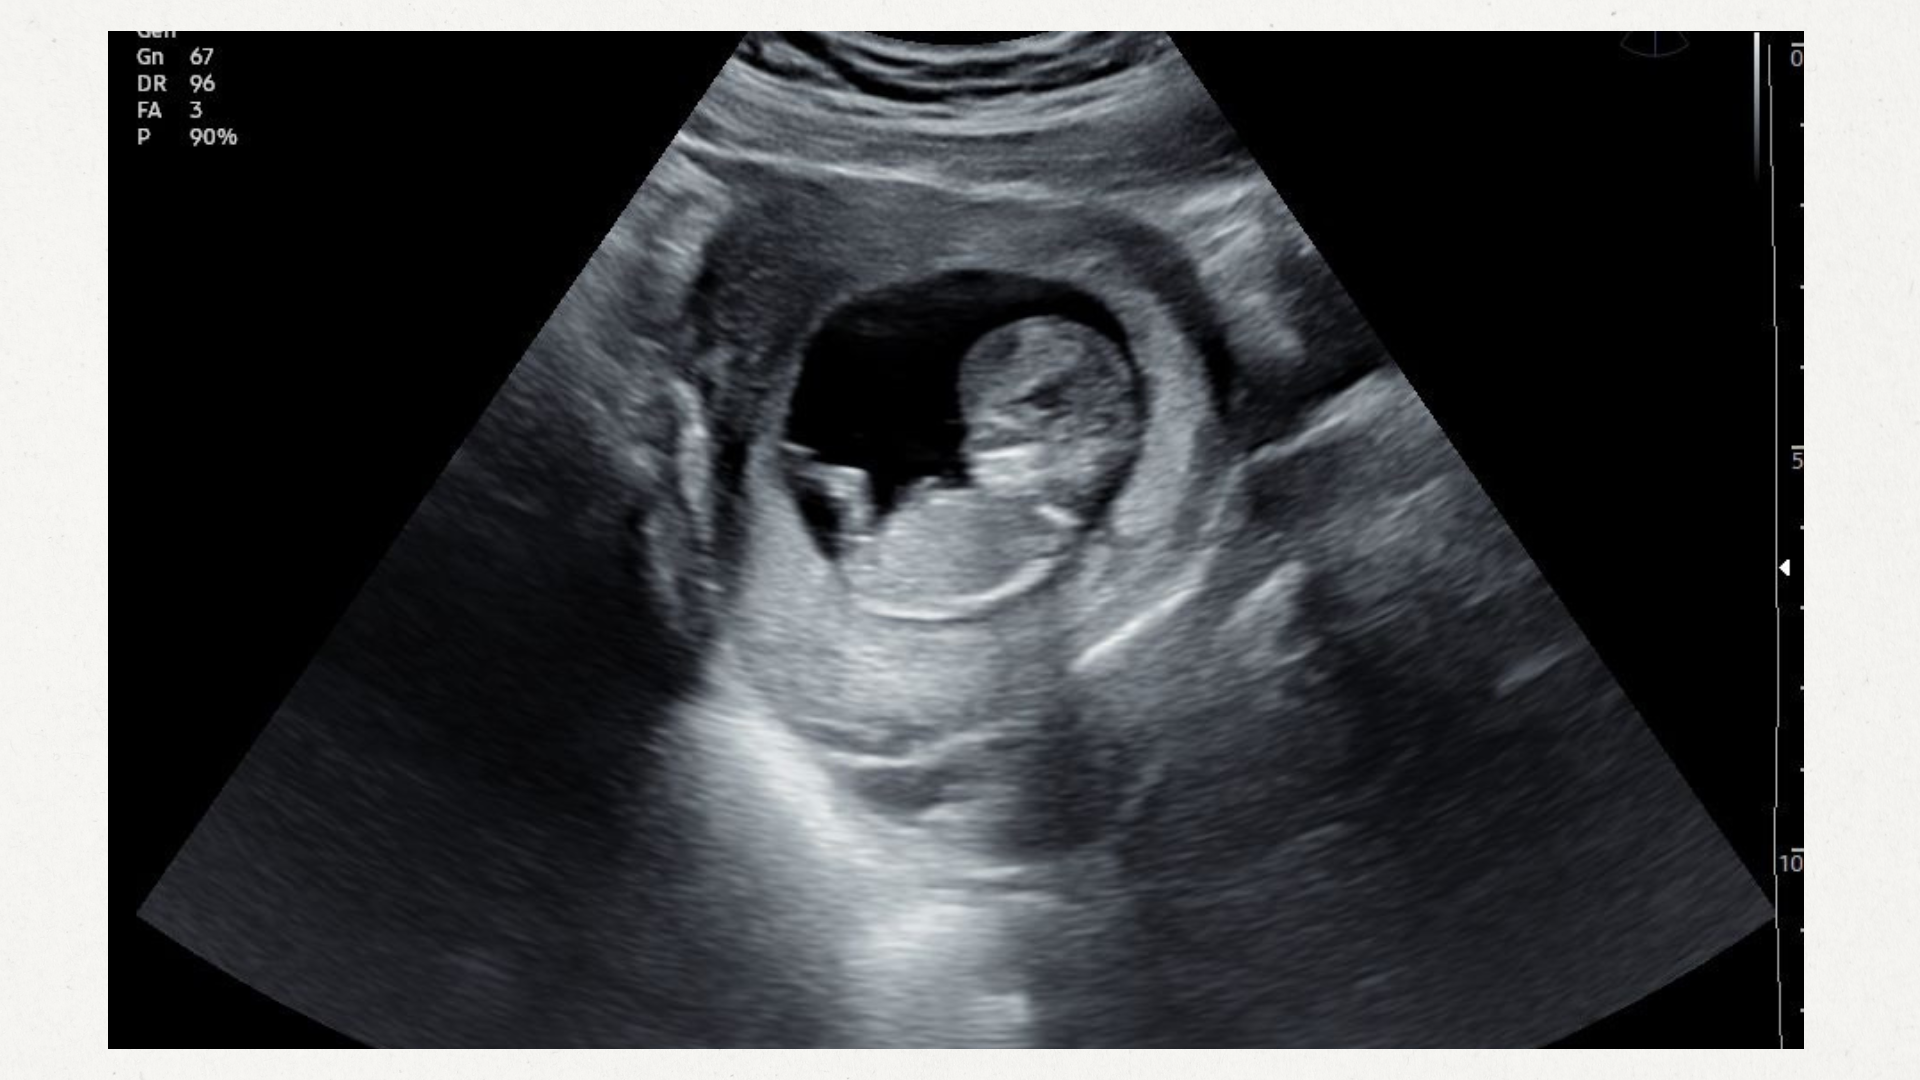

Hoe bijzonder is het om je baby op een rustige en intieme manier te kunnen bewonderen, gewoon bij jou thuis? Vanuit je eigen zetel volg je alles vanop je televisie, terwijl ik mooie beeldjes van je baby maak. Zo kan je in alle comfort samen met je partner, familie of vrienden genieten van een warm en ontspannen moment, zonder verplaatsing, wachtzaal of gehaast.

Tijdens de pretecho neem ik rustig de tijd om niet alleen je baby te tonen, maar ook om op een toegankelijke en fijne manier uitleg te geven over de ontwikkeling van je baby en de zwangerschap. Ik deel graag leuke tips en weetjes, zodat je niet alleen kijkt, maar ook echt begrijpt wat er allemaal groeit en verandert.

PRILLE ZWANGERSCHAP (10-15 weken)

Een bijzonder moment om de bewegingen van je kindje te bewonderen, nog voor je ze zelf kan voelen.

ZWANGERSCHAP (16-35 weken)

Een mooi moment om je baby opnieuw te bewonderen.

*De beeldkwaliteit kan per echo verschillen en hangt af van verschillende factoren zoals de ligging van je baby, de positie van de placenta, de zwangerschapsduur, de hoeveelheid vruchtwater,...